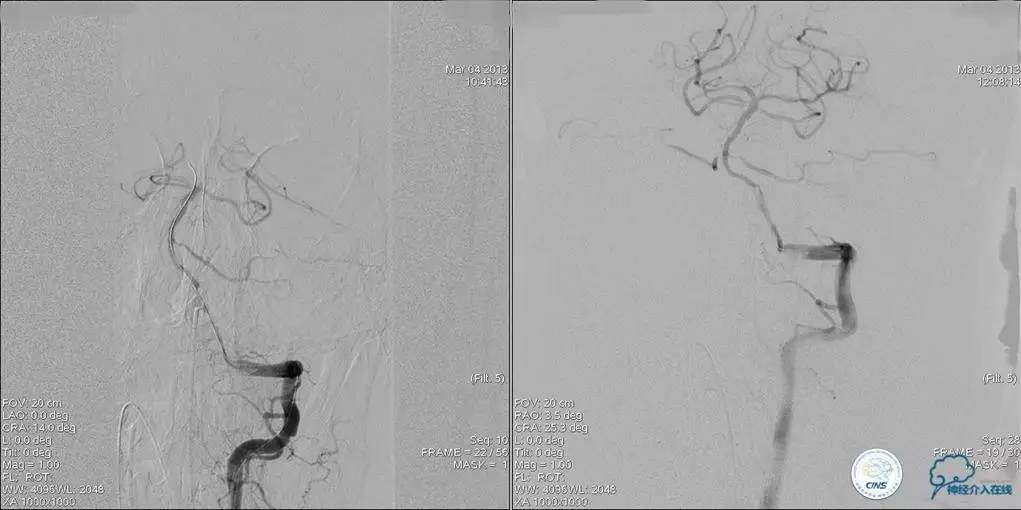

▼术前DSA

▼术中DSA

▼术后DSA